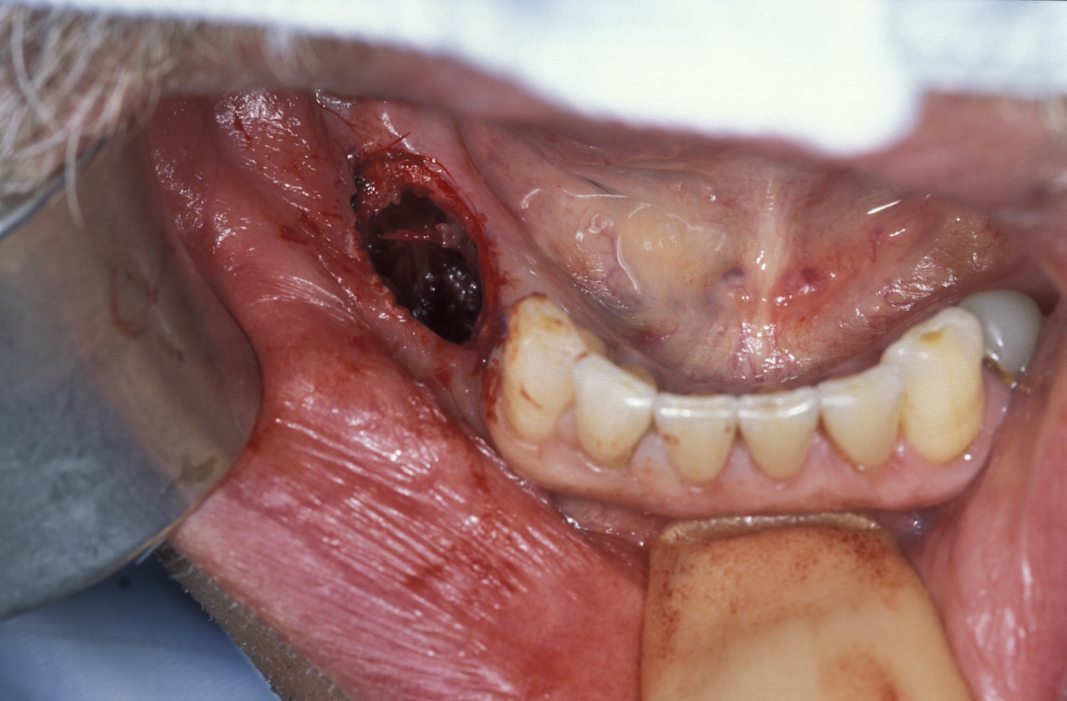

Enucleation involves the stripping away of the cyst lining from the resorbed bony cavity, resulting in a clean ‘hole’ in the bone. This deficit is filled by blood which organises into osteoid and then into new bone. There has never been an evidence-based demonstration of need to graft or fill the defect with synthetic substances. A step by step illustration of the procedure is shown in Figures 1 to 6.

Figure 5: The empty bone cavity after removal of the cyst.

Figure 6: The removed cyst specimen.